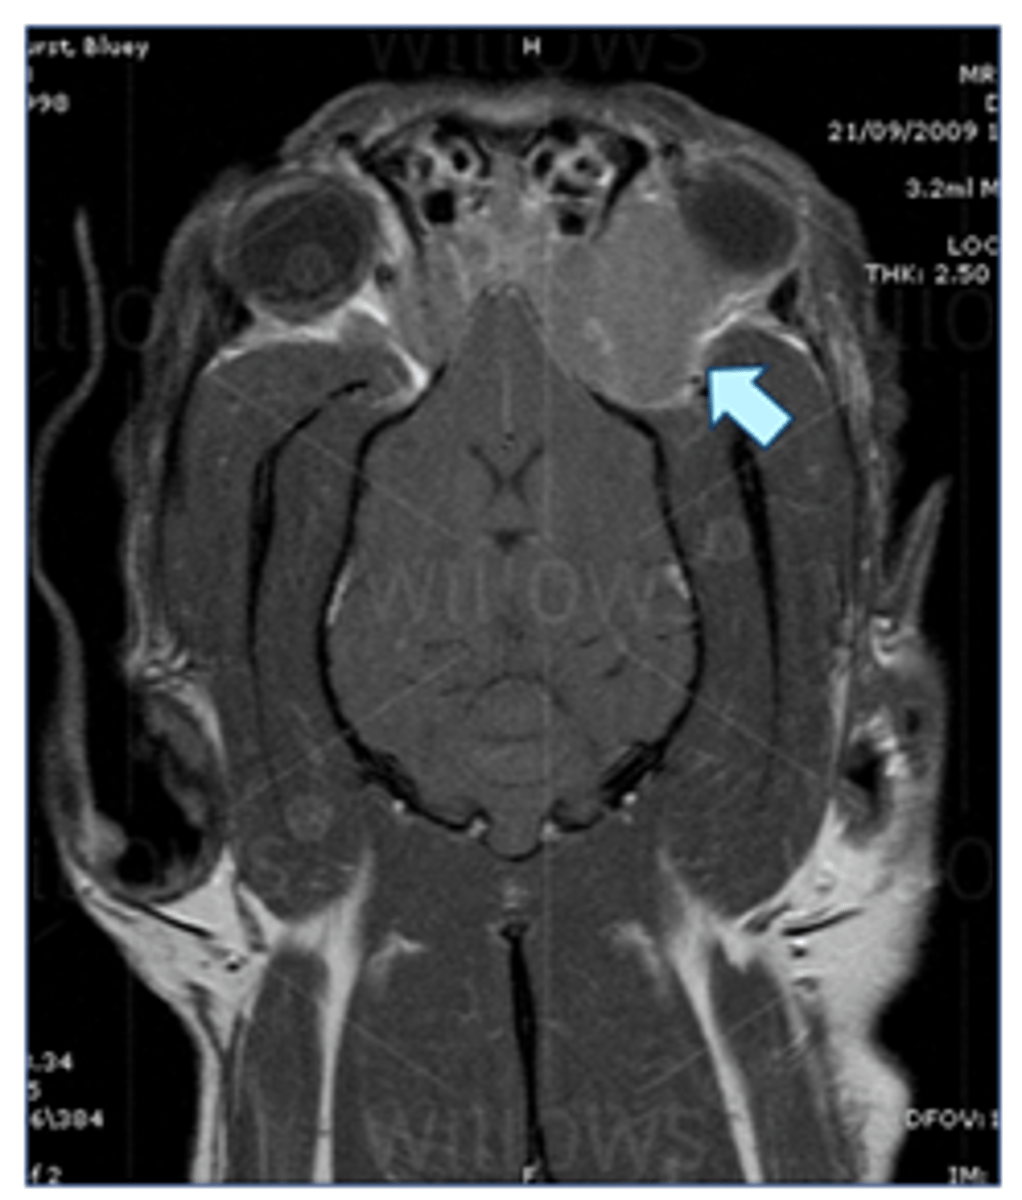

MRI –tumour behind eye (retrobulbar tumour)